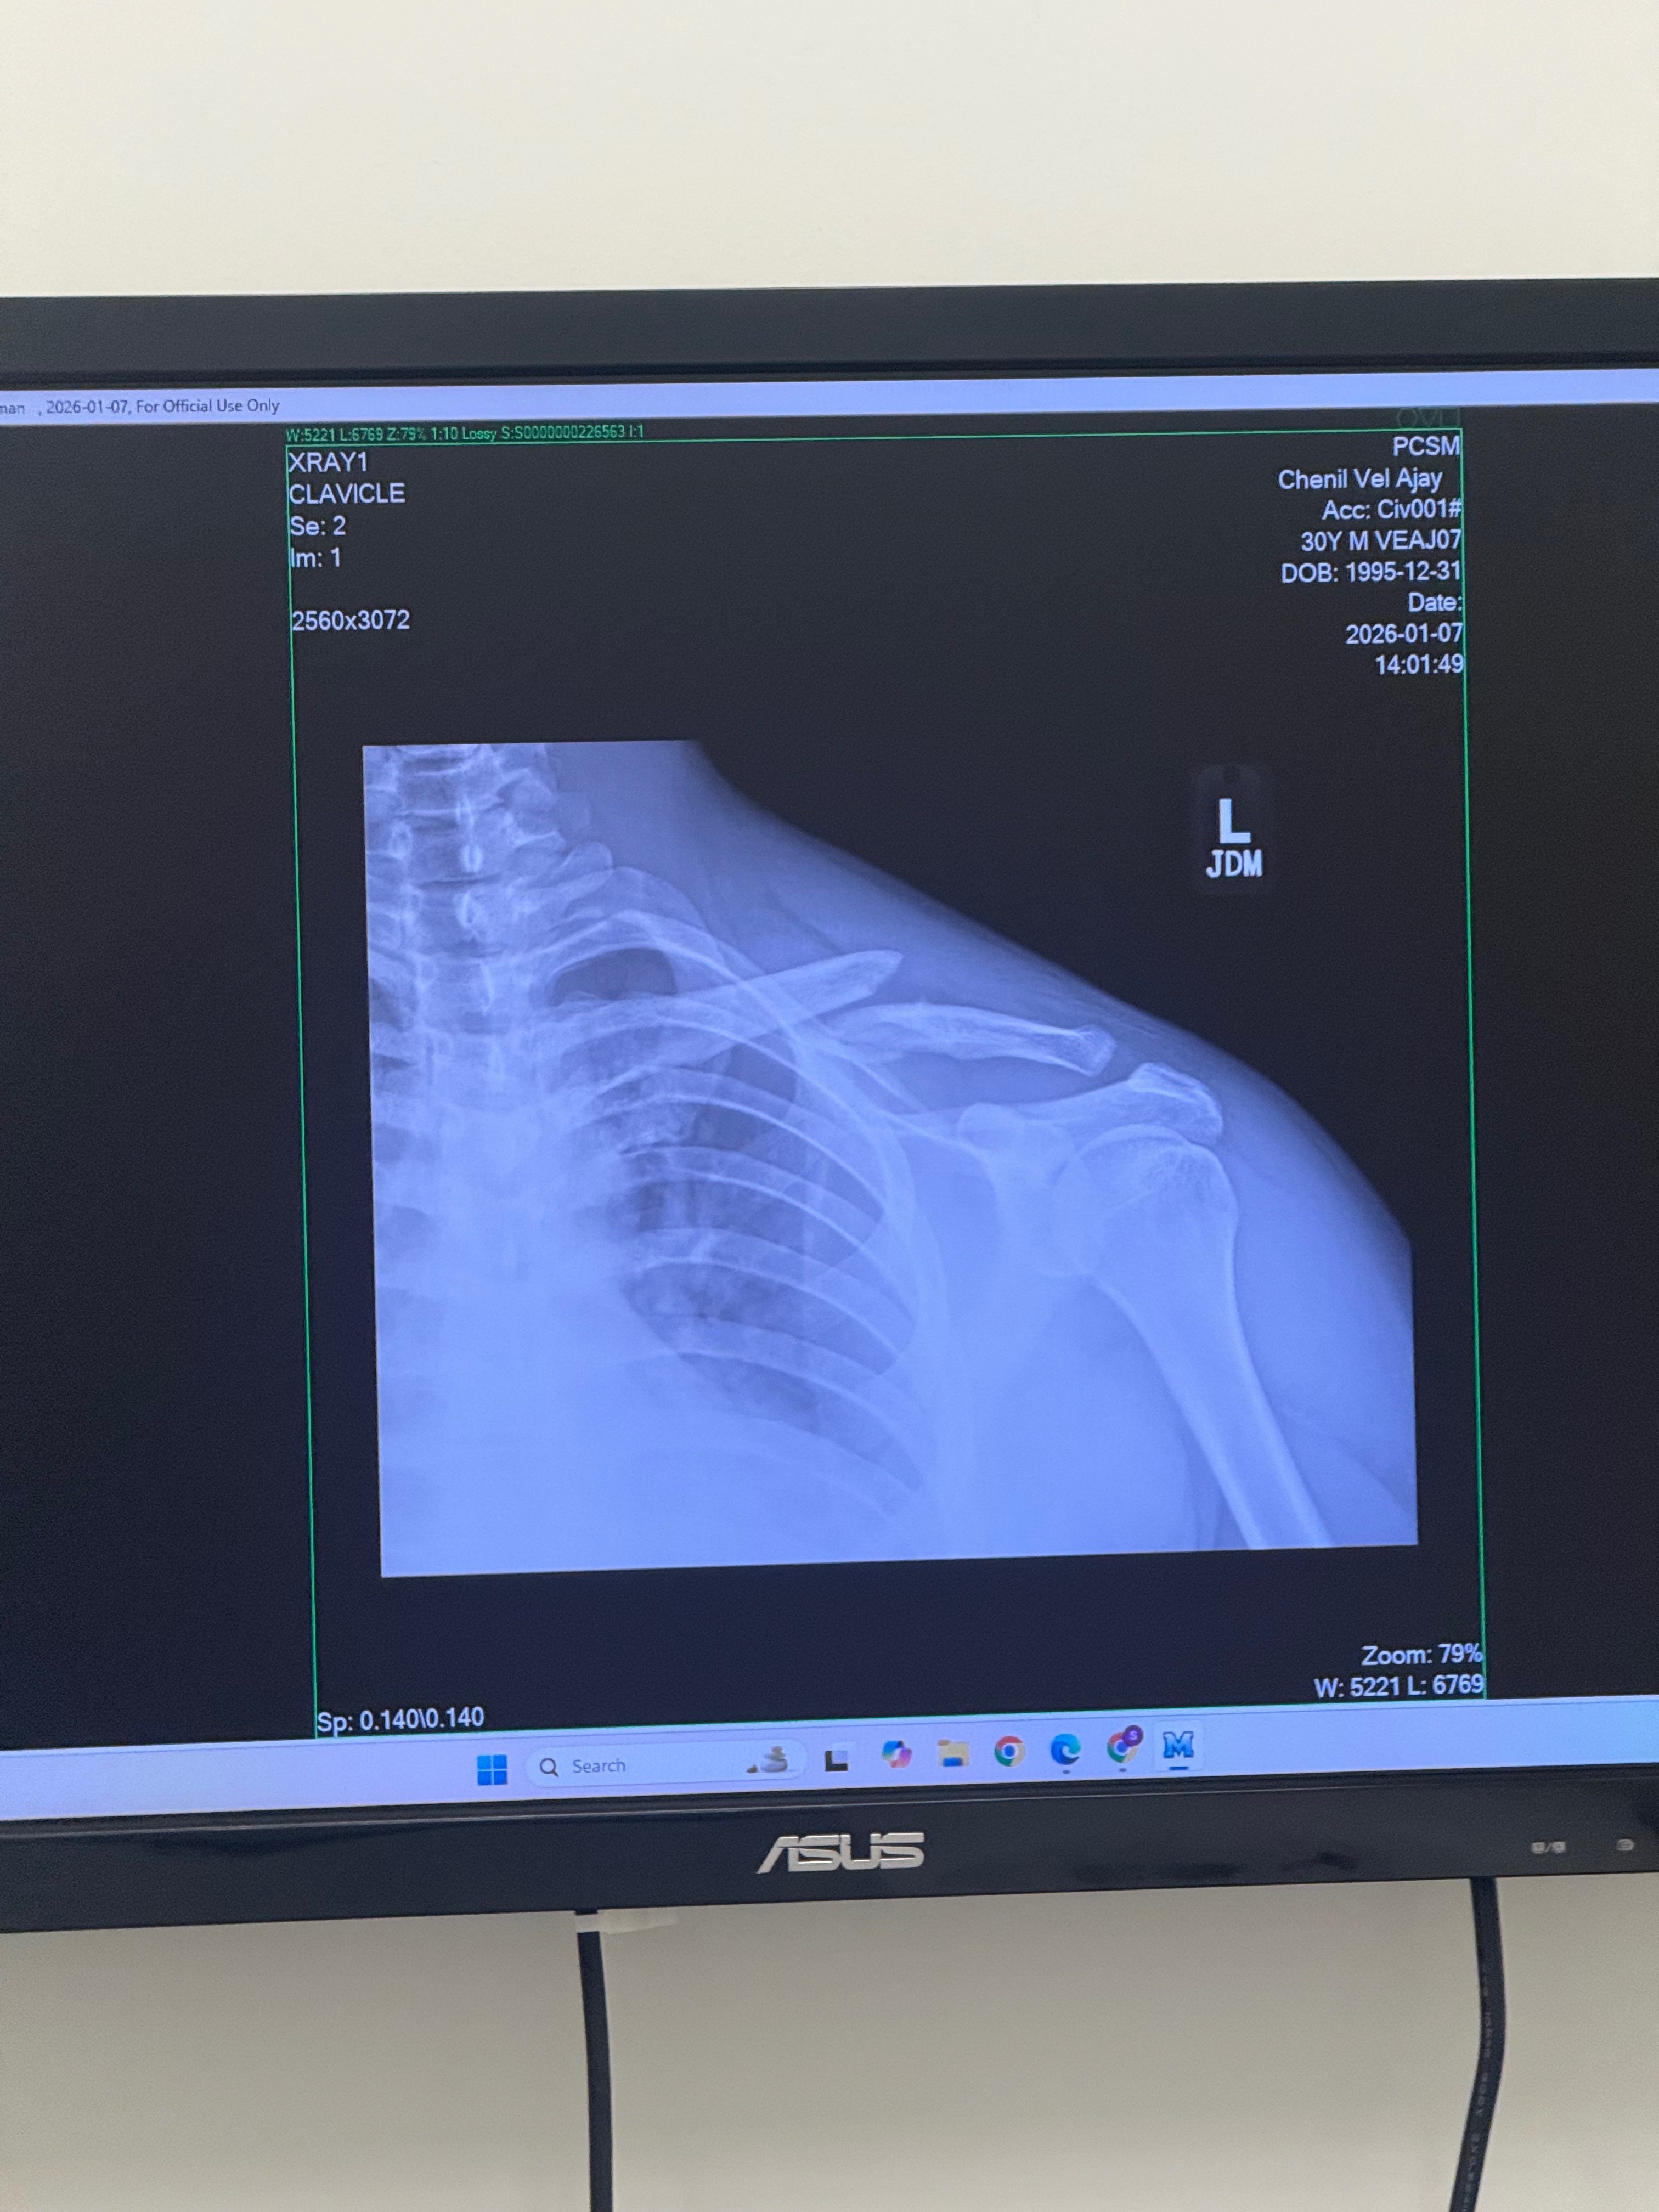

On December 29th, my life took an unexpected turn when I was hit by a car while riding a Lime scooter. The accident left me with a broken clavicle and significant bruising on my hips and legs. As a result, I need surgery on my collar bone and have been unable to attend work. Not having health insurance has made this situation even more challenging, as the medical bills and daily living expenses are quickly adding up.